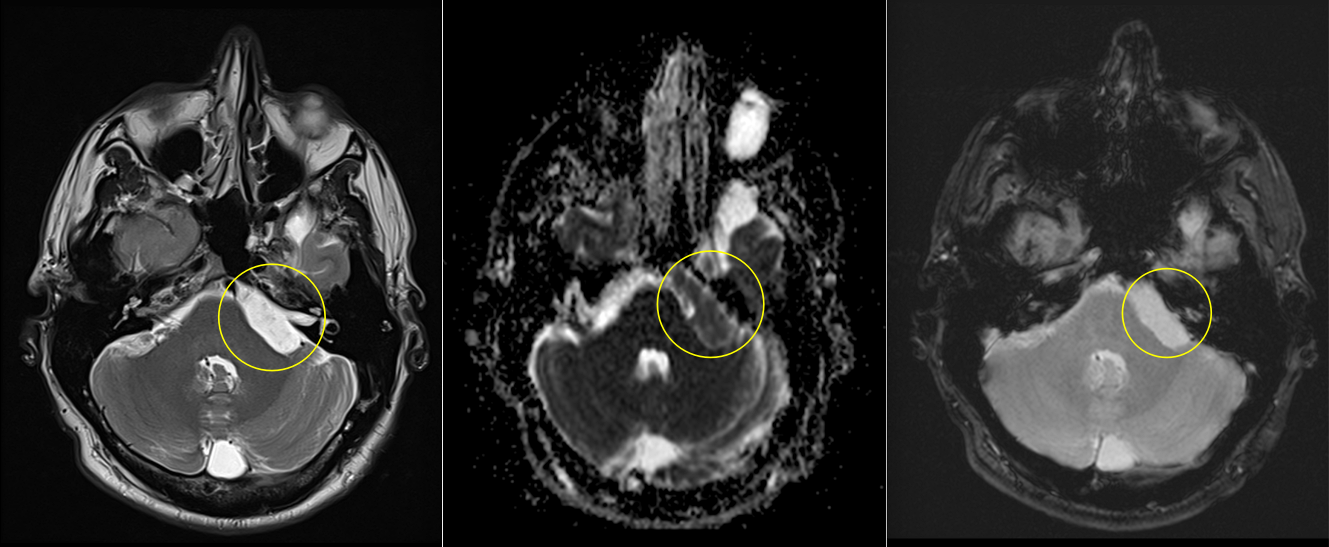

Imagistica prin rezonanță magnetică (IRM):

- Investigația de elecție.

- Chisturile epidermoide:

- Hiposemnal T1, hipersemnal T2.

- Nu se încarcă cu substanță de contrast.

- Apare restricție de difuzie pe secvențele DWI – caracteristică importantă.

- Chisturile dermoide:

- Hipersemnal pe T1 (datorită conținutului lipidic).

- Semnal mixt pe T2.

- Poate avea semnal susceptibil pe secvențe GRE dacă există componente calcificate.

- Poate fi evidentă o fistulă cu exteriorul.